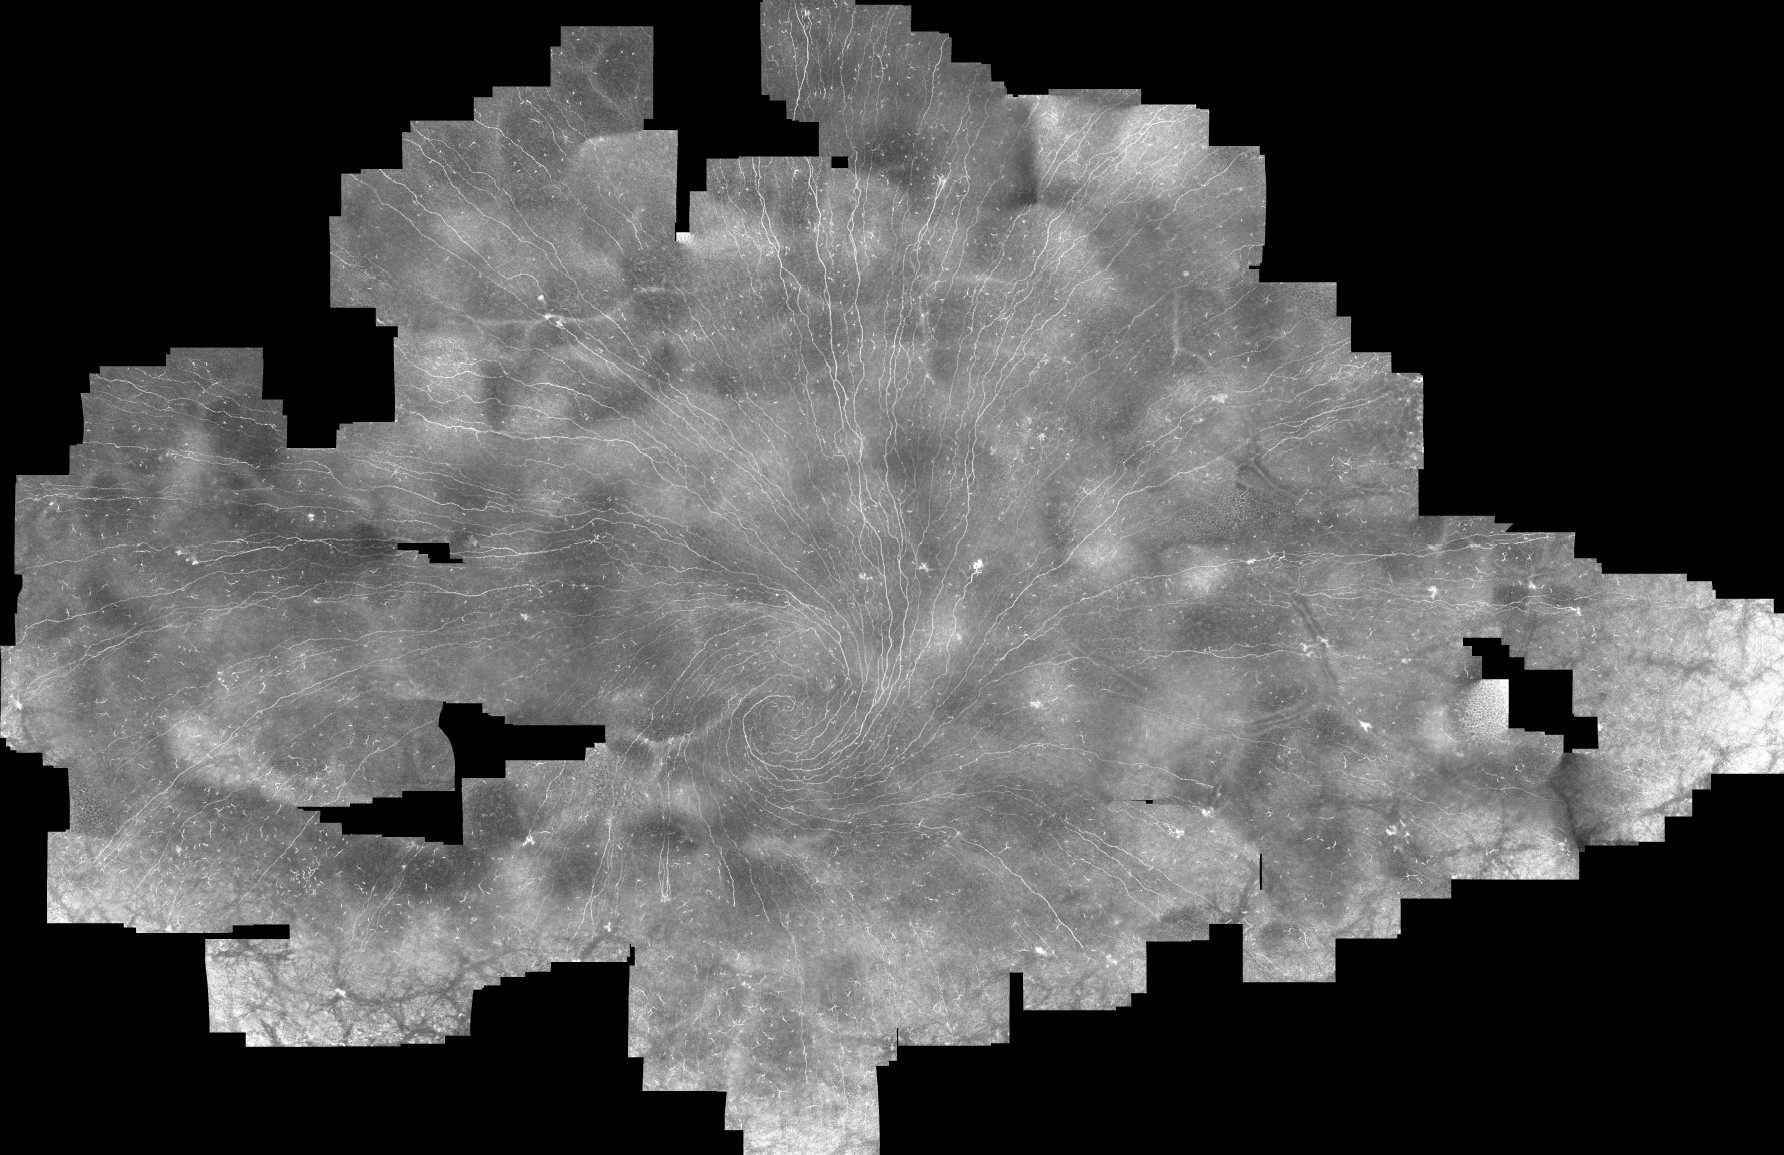

• Assoziation zwischen Hornhautnervenfunktion, -morphologie und dem Trockenen Auge (DED)

Assoziation zwischen Hornhautnervenfunktion, -morphologie und dem Trockenen Auge (DED)

107.png

Screenshot 2025-10-29 090331.png

Screenshot 2025-10-29 101808.jpg